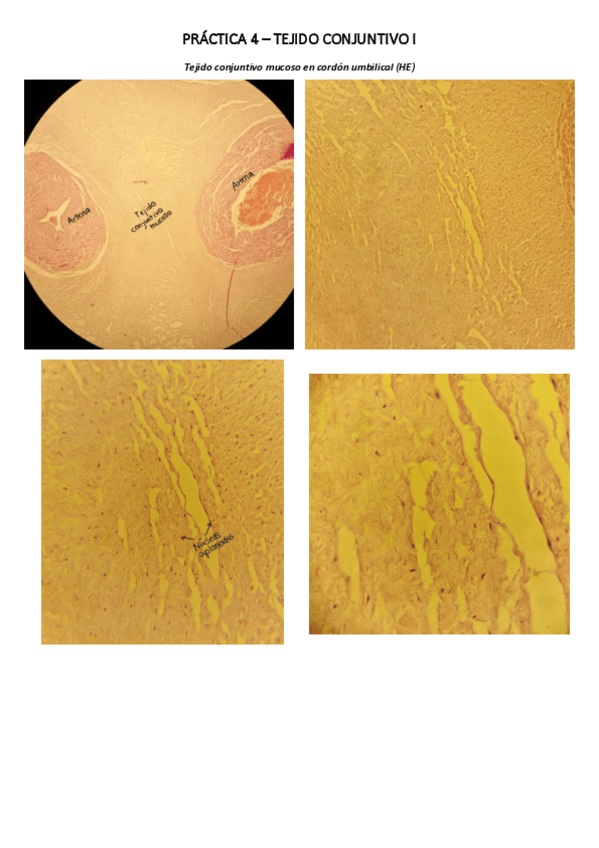

Practica-4.-Tejido-conjuntivo-I.pdf